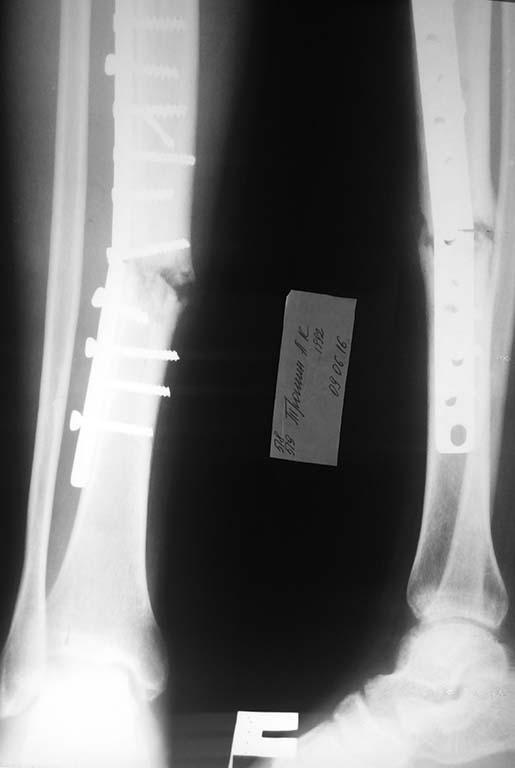

Здравствуйте, коллеги! В данном случае если просто поменять накостную пластинку, не трогая концы отломков, не повлияет ли это на костное сращение???

Больной оперирован в Феврале 2016г. Не соблюдая рекомендации, ходил без костылей. В начале Июня сломал пластинку. Ваше мнение?

Если вы повторите такой же остеосинтез - сломается опять! Слишком много винтов, слишком близко винты к зоне перелома, пересинтезировать однозначно либо штифтом с рассверливанием, либо накостно по канона. АО.